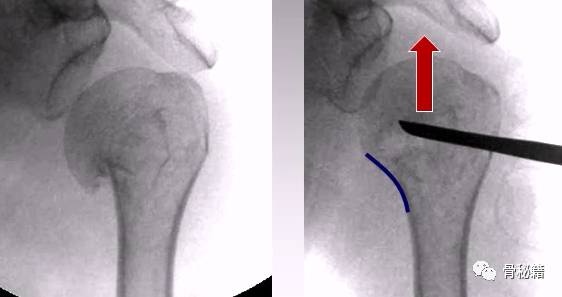

正位的翘拨复位

腋位的翘拨复位

2、用骨拨进行头下翘拨复位

1、内侧需要完成支撑,复位肱骨距,翘拨要完成正位、侧位、腋位的综合复位